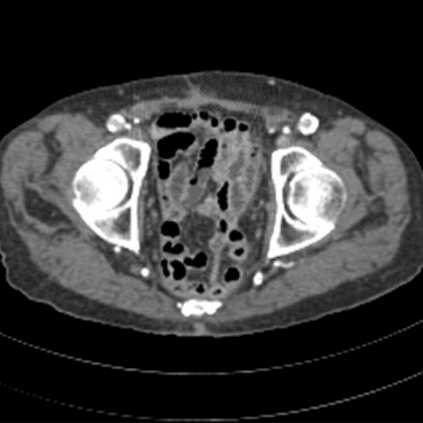

Sparse-view computed tomography (CT) -- using a small number of projections for tomographic reconstruction -- enables much lower radiation dose to patients and accelerated data acquisition. The reconstructed images, however, suffer from strong artifacts, greatly limiting their diagnostic value. Current trends for sparse-view CT turn to the raw data for better information recovery. The resultant dual-domain methods, nonetheless, suffer from secondary artifacts, especially in ultra-sparse view scenarios, and their generalization to other scanners/protocols is greatly limited. A crucial question arises: have the image post-processing methods reached the limit? Our answer is not yet. In this paper, we stick to image post-processing methods due to great flexibility and propose global representation (GloRe) distillation framework for sparse-view CT, termed GloReDi. First, we propose to learn GloRe with Fourier convolution, so each element in GloRe has an image-wide receptive field. Second, unlike methods that only use the full-view images for supervision, we propose to distill GloRe from intermediate-view reconstructed images that are readily available but not explored in previous literature. The success of GloRe distillation is attributed to two key components: representation directional distillation to align the GloRe directions, and band-pass-specific contrastive distillation to gain clinically important details. Extensive experiments demonstrate the superiority of the proposed GloReDi over the state-of-the-art methods, including dual-domain ones. The source code is available at https://github.com/longzilicart/GloReDi.